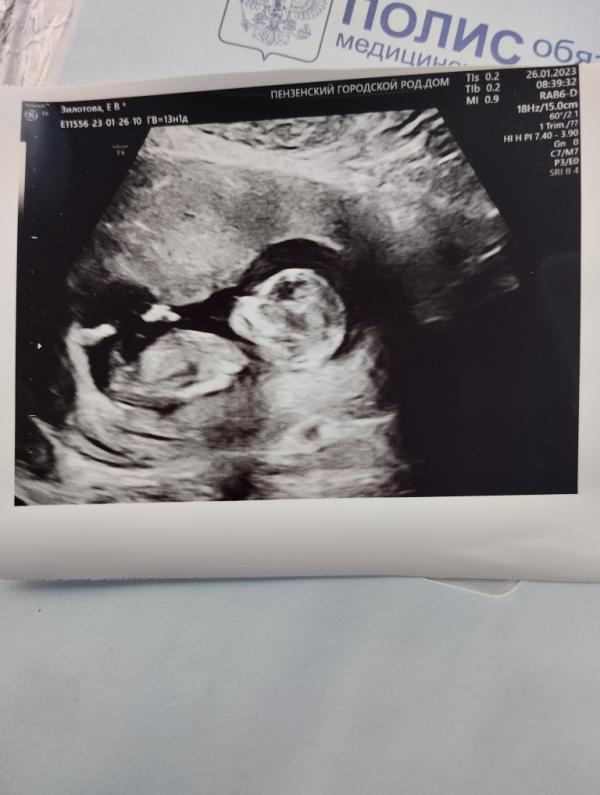

Была сегодня на 1 скрининге, слезы счастья на глазах) ногами пинался, туда сюда катался, палец сосал 😁

По узи все отлично, никаких отклонений нет, ребенок крупный, опережает свой срок, акушерский у меня 13 недель и 1 день, эмбриональный должен быть где то 11 недель, а у меня эмбриональный 13 недель и 5 дней) пол предположили, что сыночек)